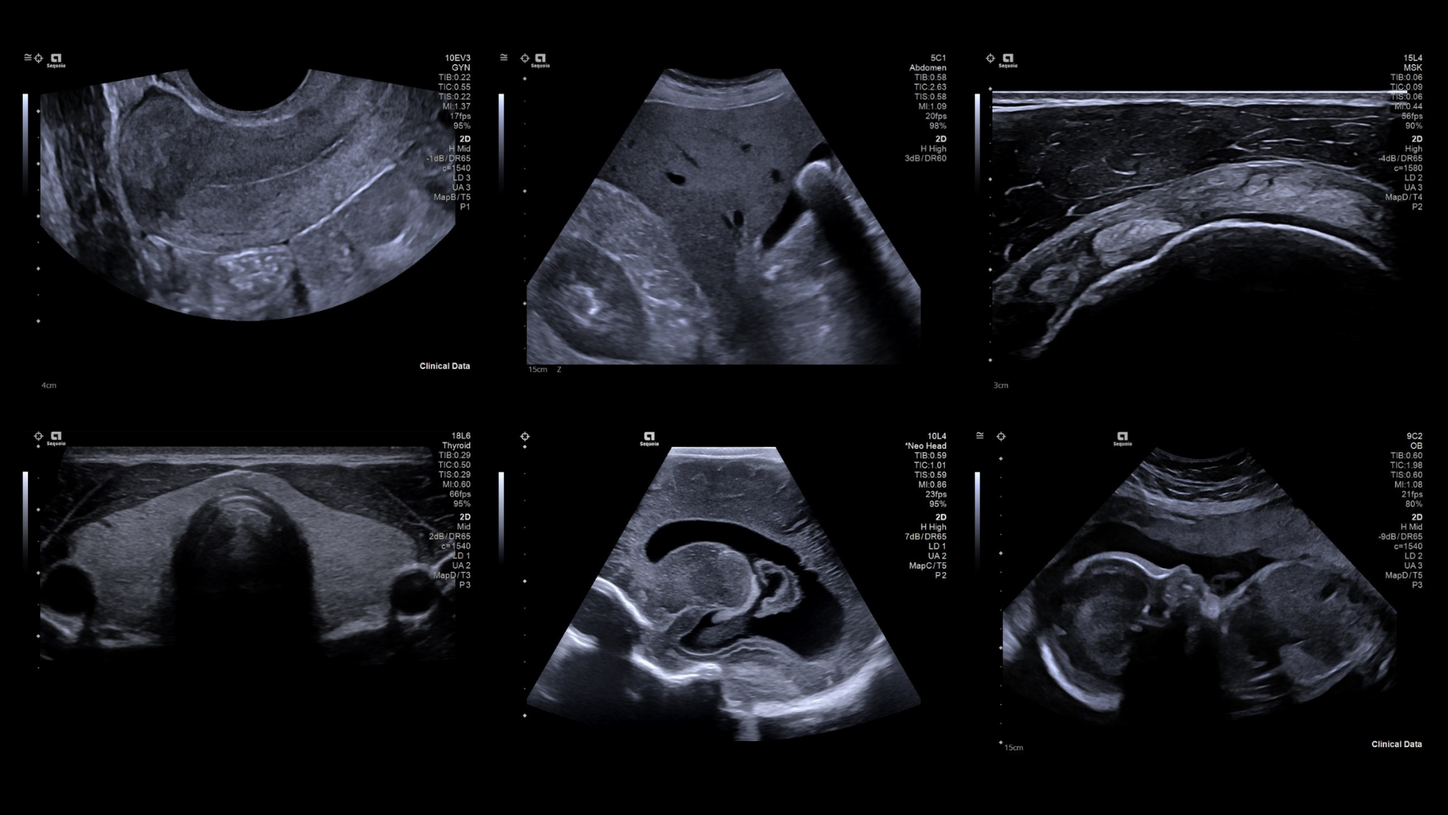

The ACUSON Sequoia is an advanced diagnostic tool that integrates cutting-edge technology and AI-powered applications to streamline diagnostic processes. This system is designed to cater to patient-specific needs, ensuring accuracy and efficiency in various clinical settings such as Radiology, OB/GYN, Shared Service and beyond.

The latest updates on ACUSON Sequoia use the power of groundbreaking AI for abdominal cases, includes advanced breast visualization to deliver new levels of image quality confidence, and tackles the toughest challenges in musculoskeletal imaging, all while saving your team from needless strain and pain.

ACUSON Sequoia’s new advanced features are designed to improve diagnostic confidence and workflow across a wide range of clinical settings.

ACUSON Sequoia’s InFocus imaging architecture eliminates the need for conventional focal zones to create a fully focused image faster than conventional systems. Our InFocus technology applies to all imaging transducers and exam types giving you consistent imaging across clinical segments. Some of the benefits are:

A clearer, deeper perspective with optimal acoustics for each clinical use case. Expand your assessment with advanced tools that take ultrasound beyond its traditional role.

- AI Abdomen automatically recognizes and labels 17 anatomical views and 12 routine measurements.